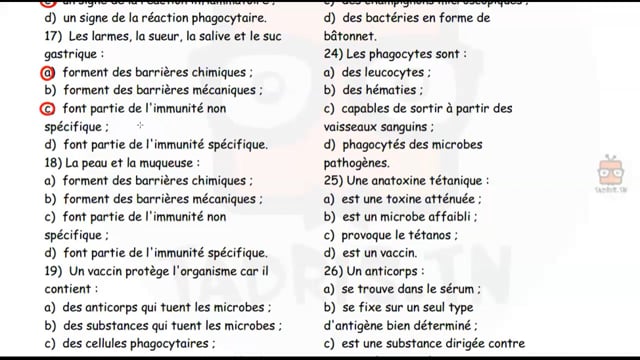

Sciences SVT

1ᴱ̀ᴿᴱ année

Enregistrement 2020-2021

Enregistrement 2021-2022

Enregistrement 2022-2023